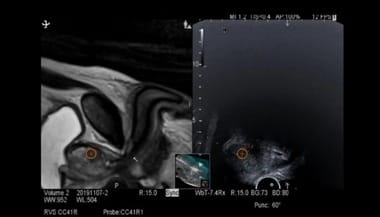

Unitatea medicală transmite că biopsia RMN-fusion combină imagistica prin rezonanţă magnetică multiparametrică (IRM/mp) cu ghidarea ecografică transrectală, permiţând medicului să identifice şi să preleveze ţesut exact din zonele suspecte identificate ale prostatei. Astfel, precizia diagnosticului creşte semnificativ.

Principiul procedurii se bazează pe suprapunerea imaginilor obţinute anterior prin RMN peste imaginile ecografice în timp real. Software-ul dedicat fuzionează cele două seturi de date, generând o hartă tridimensională detaliată a prostatei. Această abordare permite prelevarea ţintită a probelor din leziunile cu risc crescut, identificate anterior prin RMN ca fiind suspecte conform scorului PIRADS.